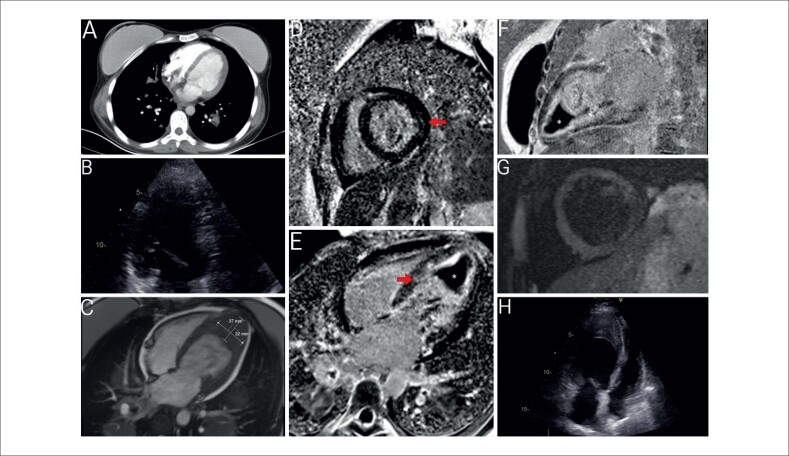

Surprising Cardiac Magnetic Resonance Imaging Findings: Rapidly Developing Intracardiac Thrombus with Endomyocardial Fibrosis.